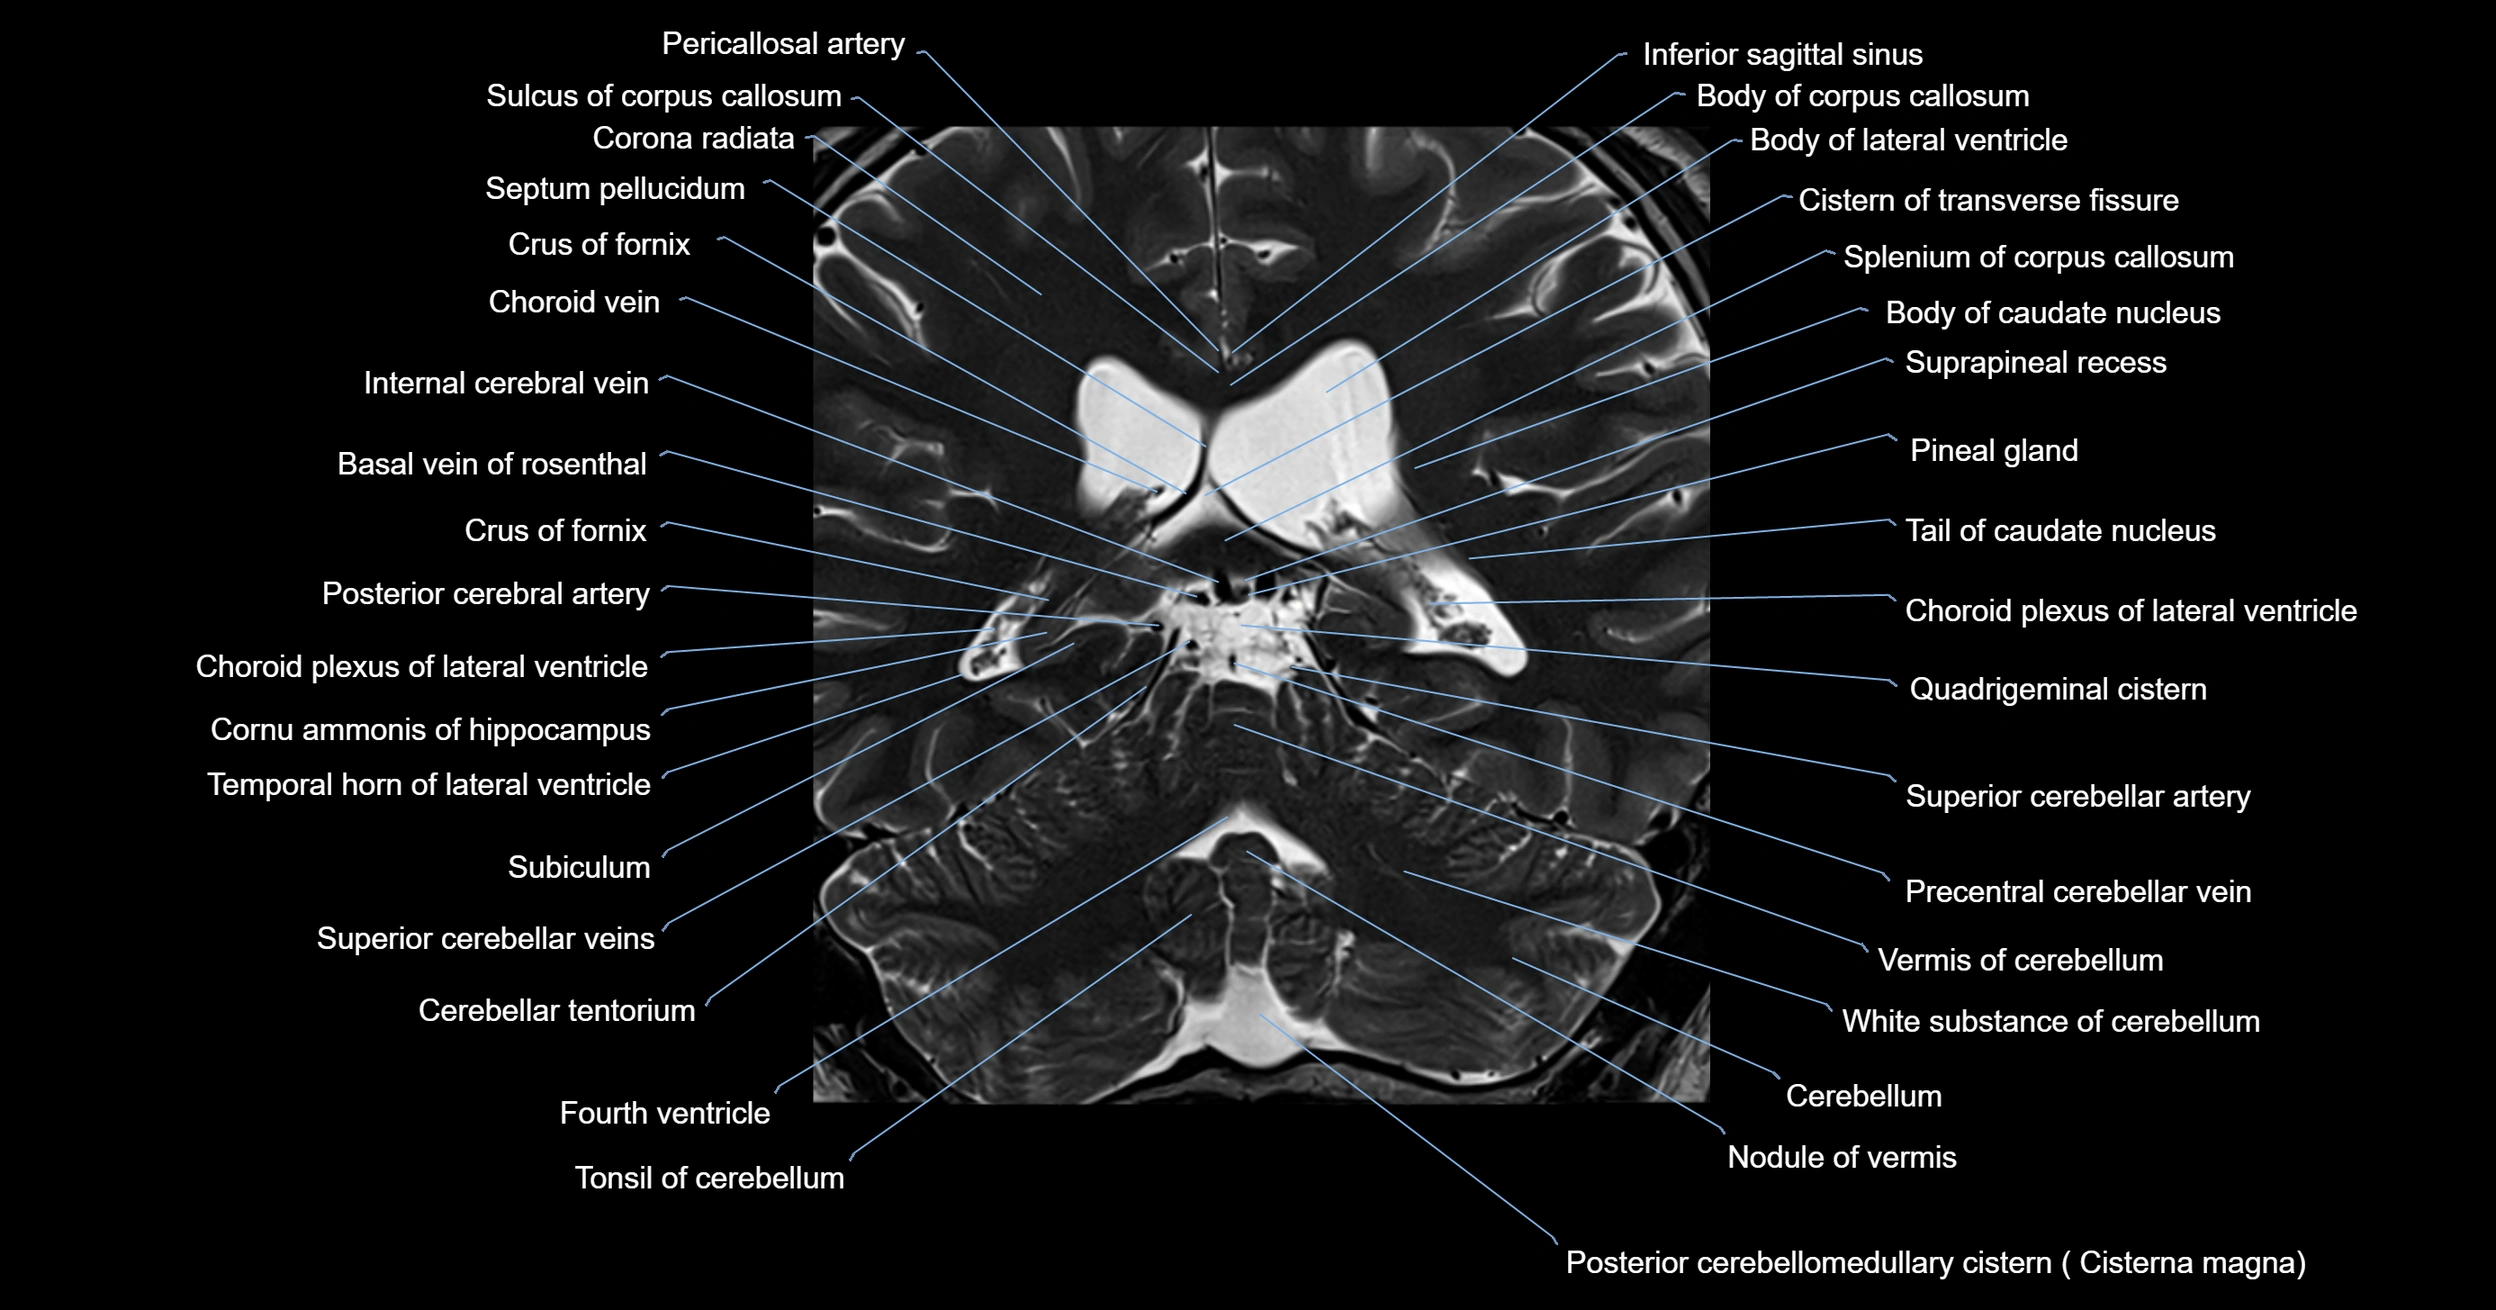

MRI images